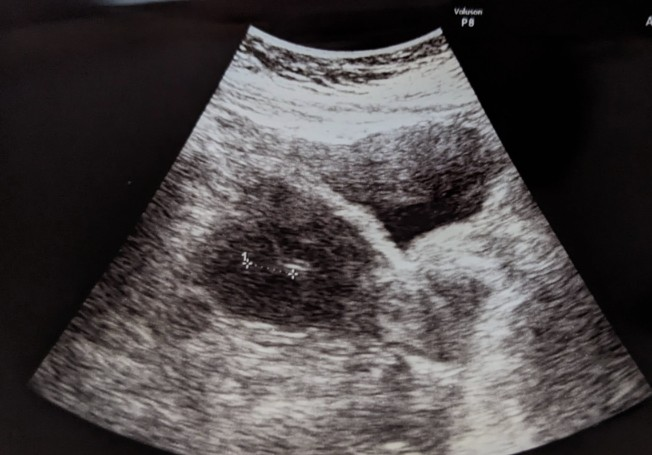

移植直後のエコー写真もらいました。

印が付けられてる真ん中の白いのが入れた卵らしい🥚

今赤ちゃんの卵がお腹の中にいるんだと感慨深いものがありました。嬉しい🥹